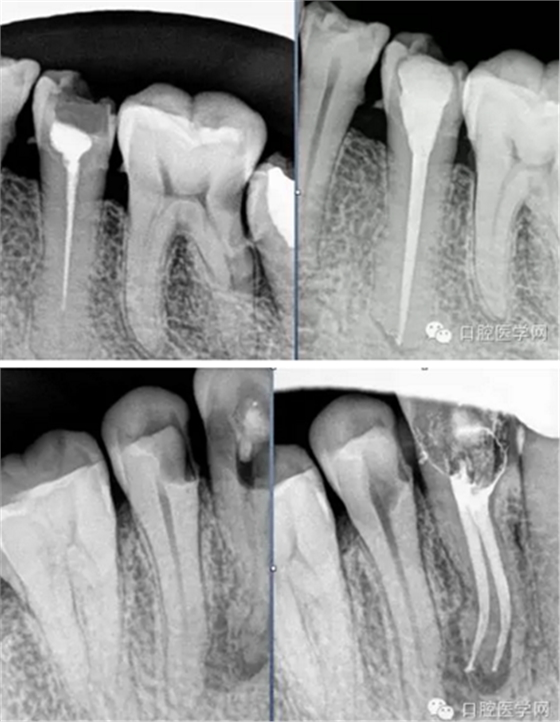

試尖(檢查是否恰填)

根充(從術(shù)后X光片可以看出根管充填完整,專業(yè)上叫恰充)

根充其實(shí)很簡單,只要前面的預(yù)備做好了,后面的充填就很順利,試尖恰好,AH樹脂湖劑+大準(zhǔn)度牙膠充填,平齊根管口將牙膠截掉,冷充的話就結(jié)束了。若要做熱充,將攜熱器頭對準(zhǔn)牙膠的中央,加熱3-4秒迅速壓入需要截斷的部位,然后等十幾秒待攜熱器桿冷卻后再加熱1-2秒取出牙膠,最后將熱牙膠注入,邊注邊壓,嚴(yán)密充填,結(jié)束。暫封一周后冠修復(fù)。通過這樣的操作牙齒就不可能發(fā)生再次感染和疼痛了。

常用標(biāo)準(zhǔn):恰充,三維致密,流暢,錐度流暢一致。

但臨床上很難從X-ray上評價一個真正的標(biāo)準(zhǔn)的根管充填。組織學(xué)的檢驗(yàn)才是金標(biāo)準(zhǔn)。幾年的追蹤,前后的對比,這些都很重要。 所以我們不能說這個牙我給你做了根管治療就一輩子沒事了,即使你按標(biāo)準(zhǔn)的程序操作,一些復(fù)雜的根管系統(tǒng)是我們不能控制的。